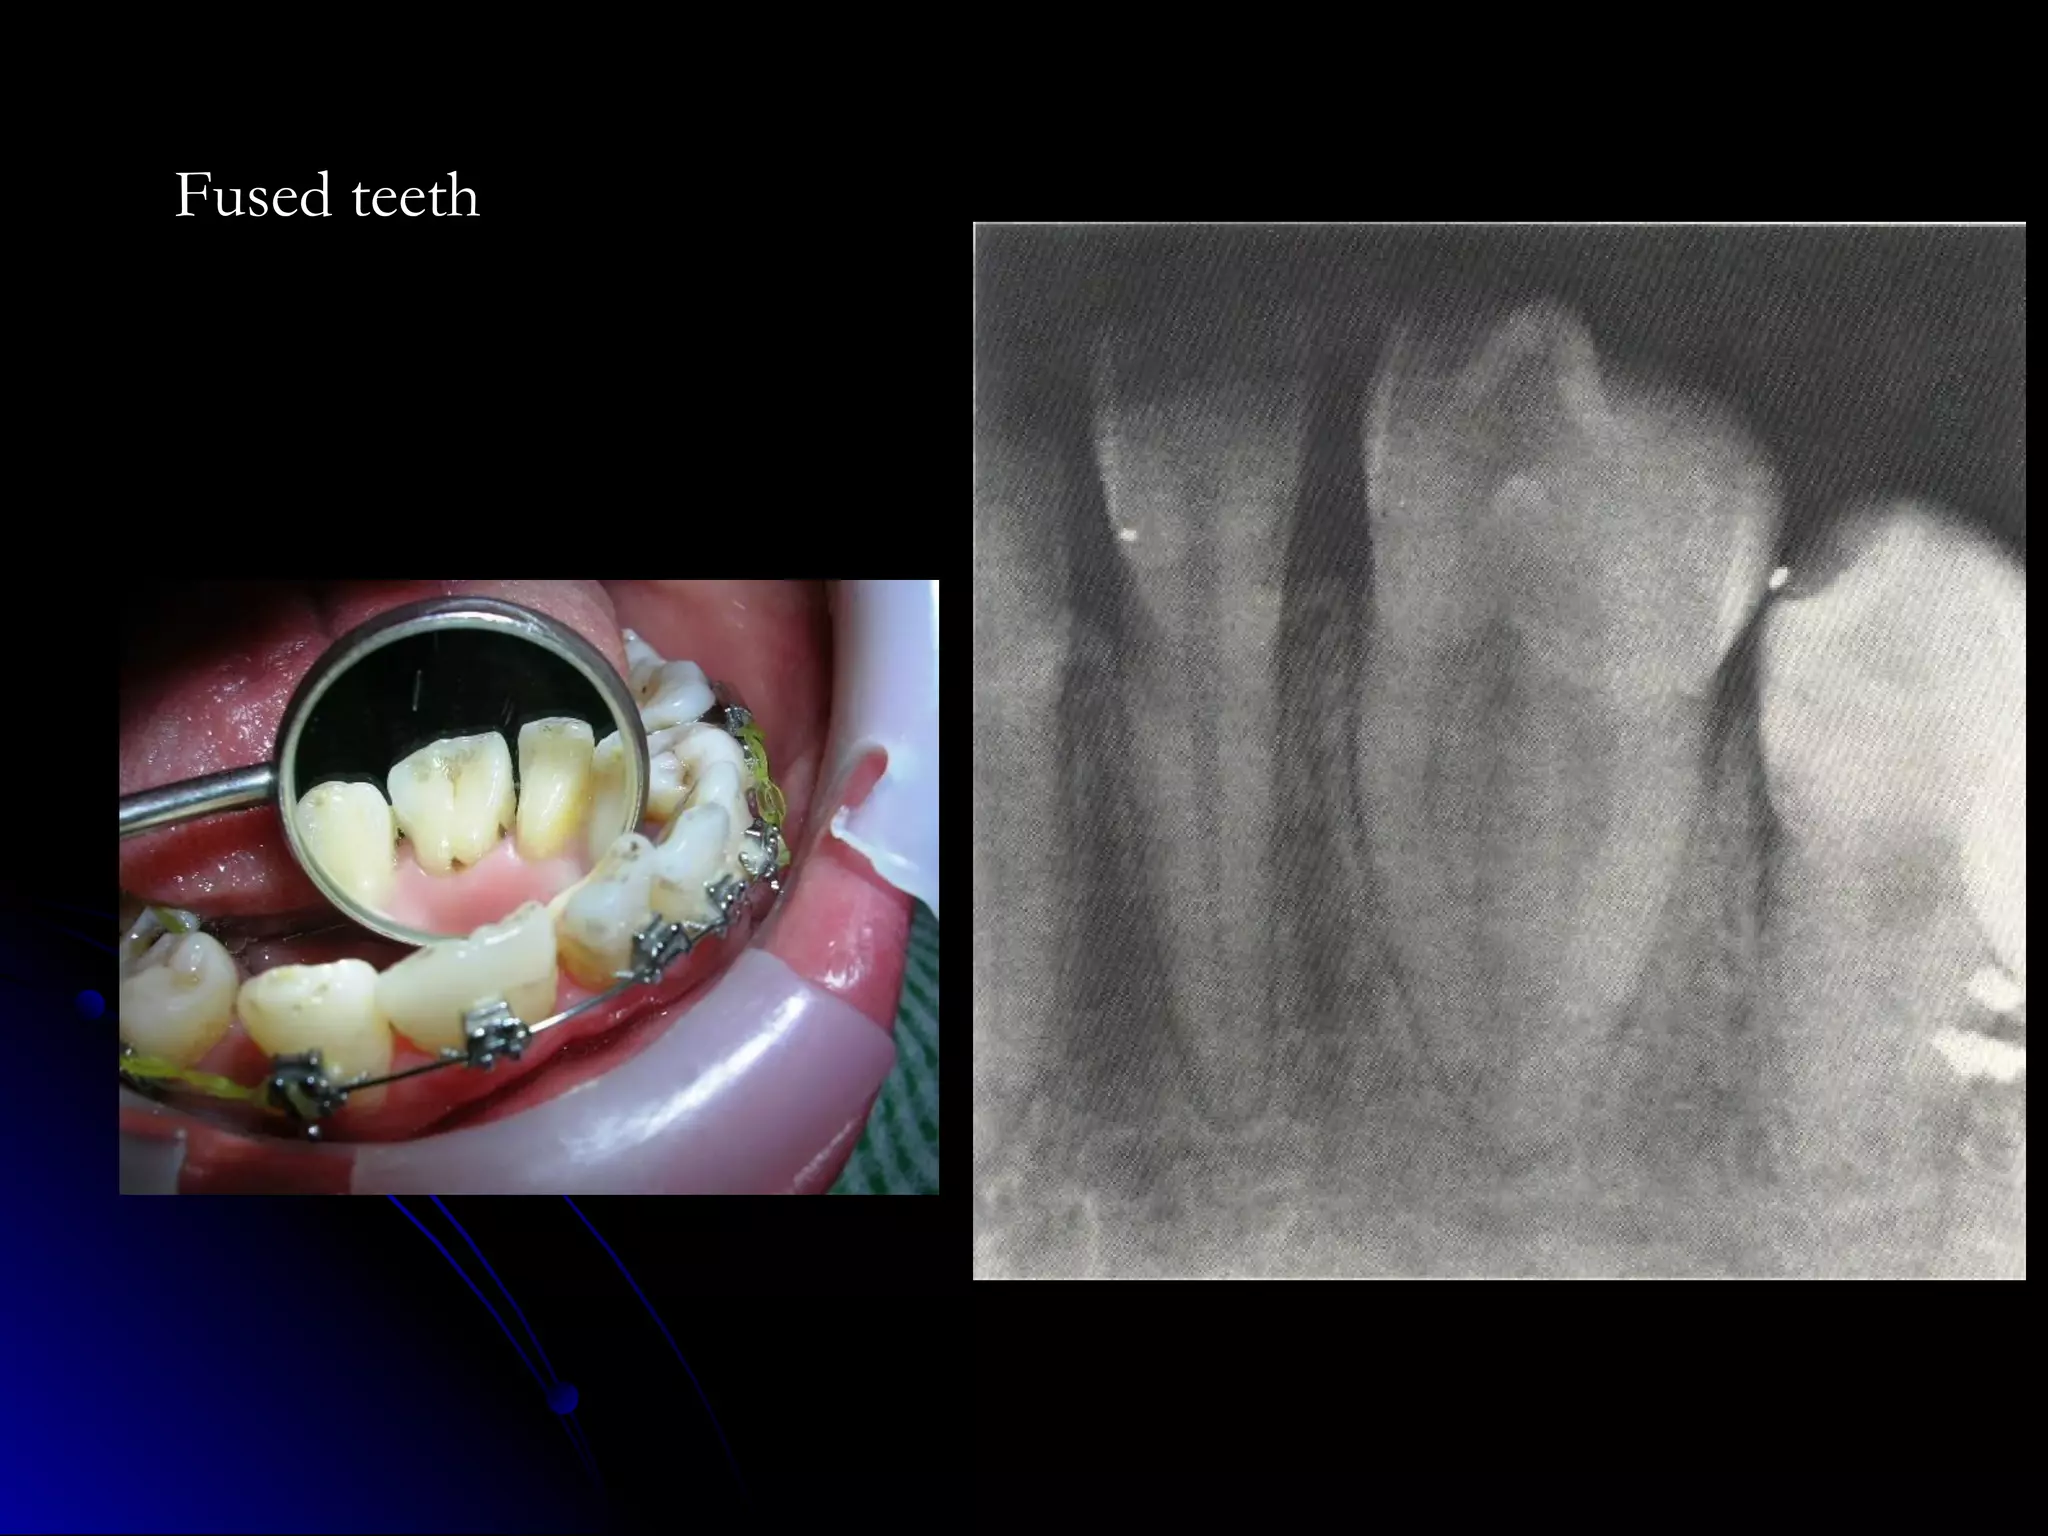

Fused teeth

ANGLE’S CLASSIFICATION OFMALOCCLUSION. CLASS I MALOCCLUSION. Mesiobuccal cusp of upper first permanent molar occludes into the buccal developmental groove of the lower first permanent molar. Line of occlusion is incorrect. There may be crowding, spacings, rotated teeth, supernumerary tooth etc.